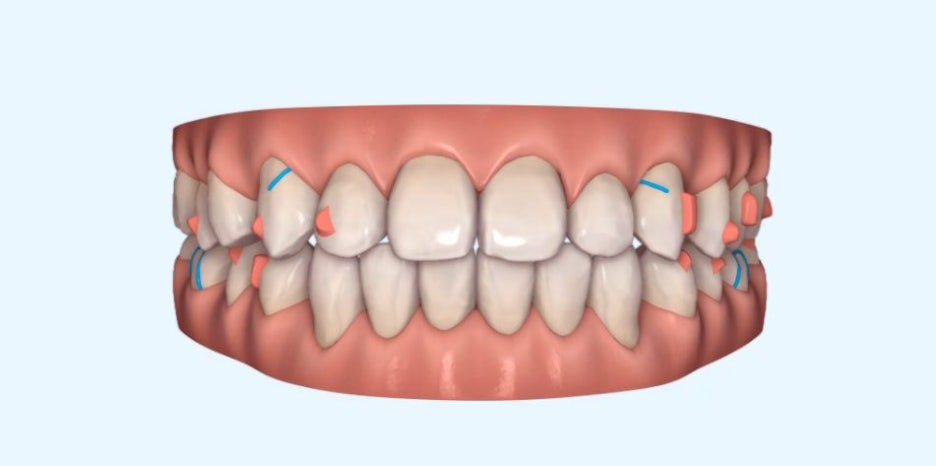

인비절라인은 치료 후 모습을 미리 예측할 수 있는

'클린체크'가 있는데요.

아래와 같이 변화된 모습을 예측하는 시스템입니다.